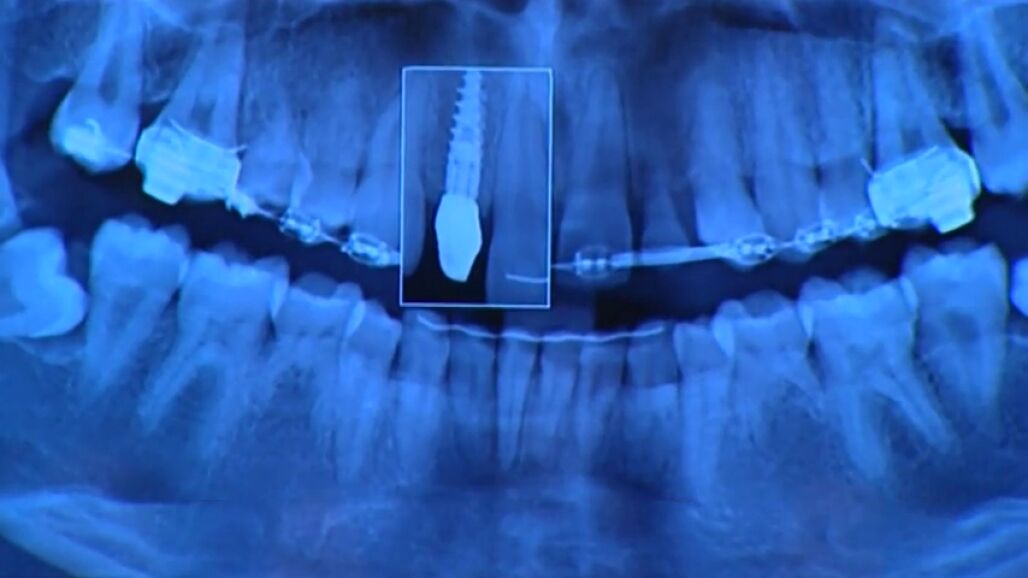

Indemnización de 2,5 millones de euros para una paciente alérgica al metal a la que se le implantó unas prótesis de cobalto

Una dentista y la compañía aseguradora deberán pagar 2,5 millones de euros de indemnización a una paciente alérgica a los metales a la que se le implantó unas prótesis de cromo-cobalto. La afectada, de 38 años, informó "personal, directa y documentalmente" a la acusada de que padecía esta alergia.

La mujer informó a la acusada de que tenía alergia a los metales y, a pesar de ello, la dentista le realizó un tratamiento con prótesis de cromo-cobalto, sin ofrecerle ninguna alternativa. Además la dentista no le informó en ningún momento del procedimiento que seguía.

Tras la operación, la paciente comenzó a sufrir infecciones, cefaleas y reacciones alérgicas. A los pocos días comenzó a notar que tenía "dificultad para el habla, la masticación y la deglución", unos síntomas a los que la dentista le contestó: "Tiene que irse acostumbrando".

Finalmente le retiraron la prótesis que le ha ocasionado lesiones de por vida, ya que no puede trabajar y apenas puede llevar una vida normal. Ella misma se califica como "una persona muerta en vida".